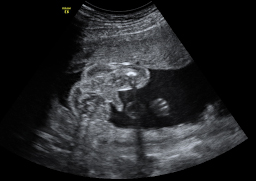

Con una edad gestacional de 20 semanas, este bebé está muy entretenido con un dedo en la boca. En esta ecografía de la semana 20, la morfológica, el especialista también mide el diámetro parietal del feto para comprobar su correcto desarrollo.

Ecografía Embarazo 4D - SEMANA 20